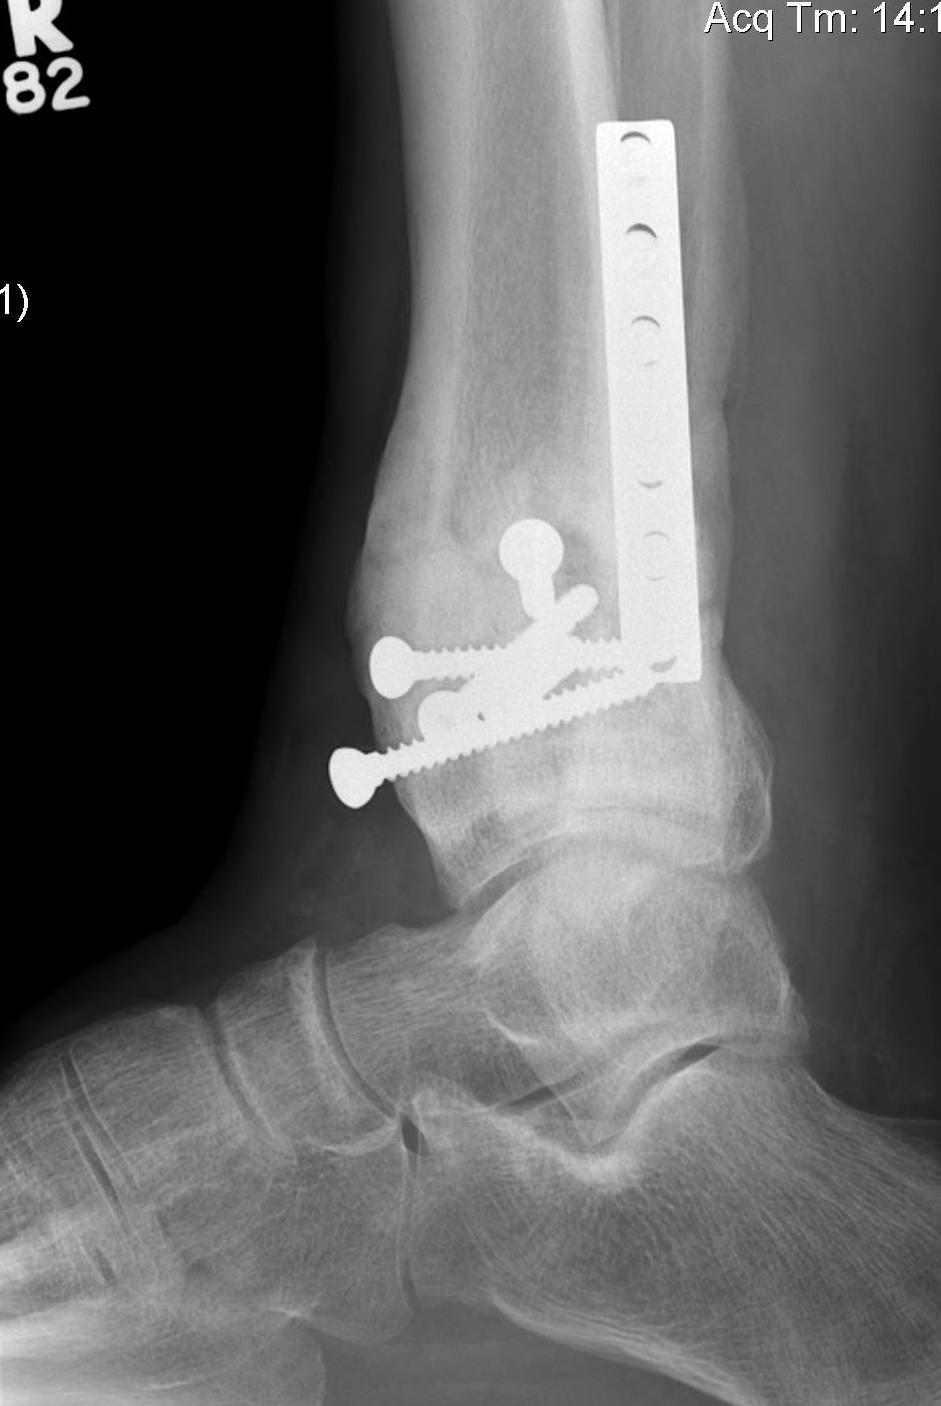

Tibial Plafond Pre External Fixator APTibial Plafond Pre External Fixator LateralTibial Plafond Post External Fixator APTibial Plafond Post External Fixator Lateral

Tibial Plafond CT AxialTibial Plafond CT SagittalPlafondTibial Plafond ORIF APTibial Plafond ORIF Lateral